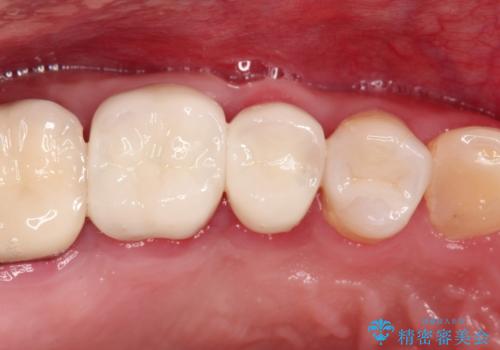

セラミッククラウン。虫歯の治療

- 定期検診にて不良補綴物、及び虫歯を認めオールセラミッククラウンにて治療を行いました。

右上第二小臼歯はカリエス除去中に露髄を認め、部分的断髄法にて歯髄を保存しております。